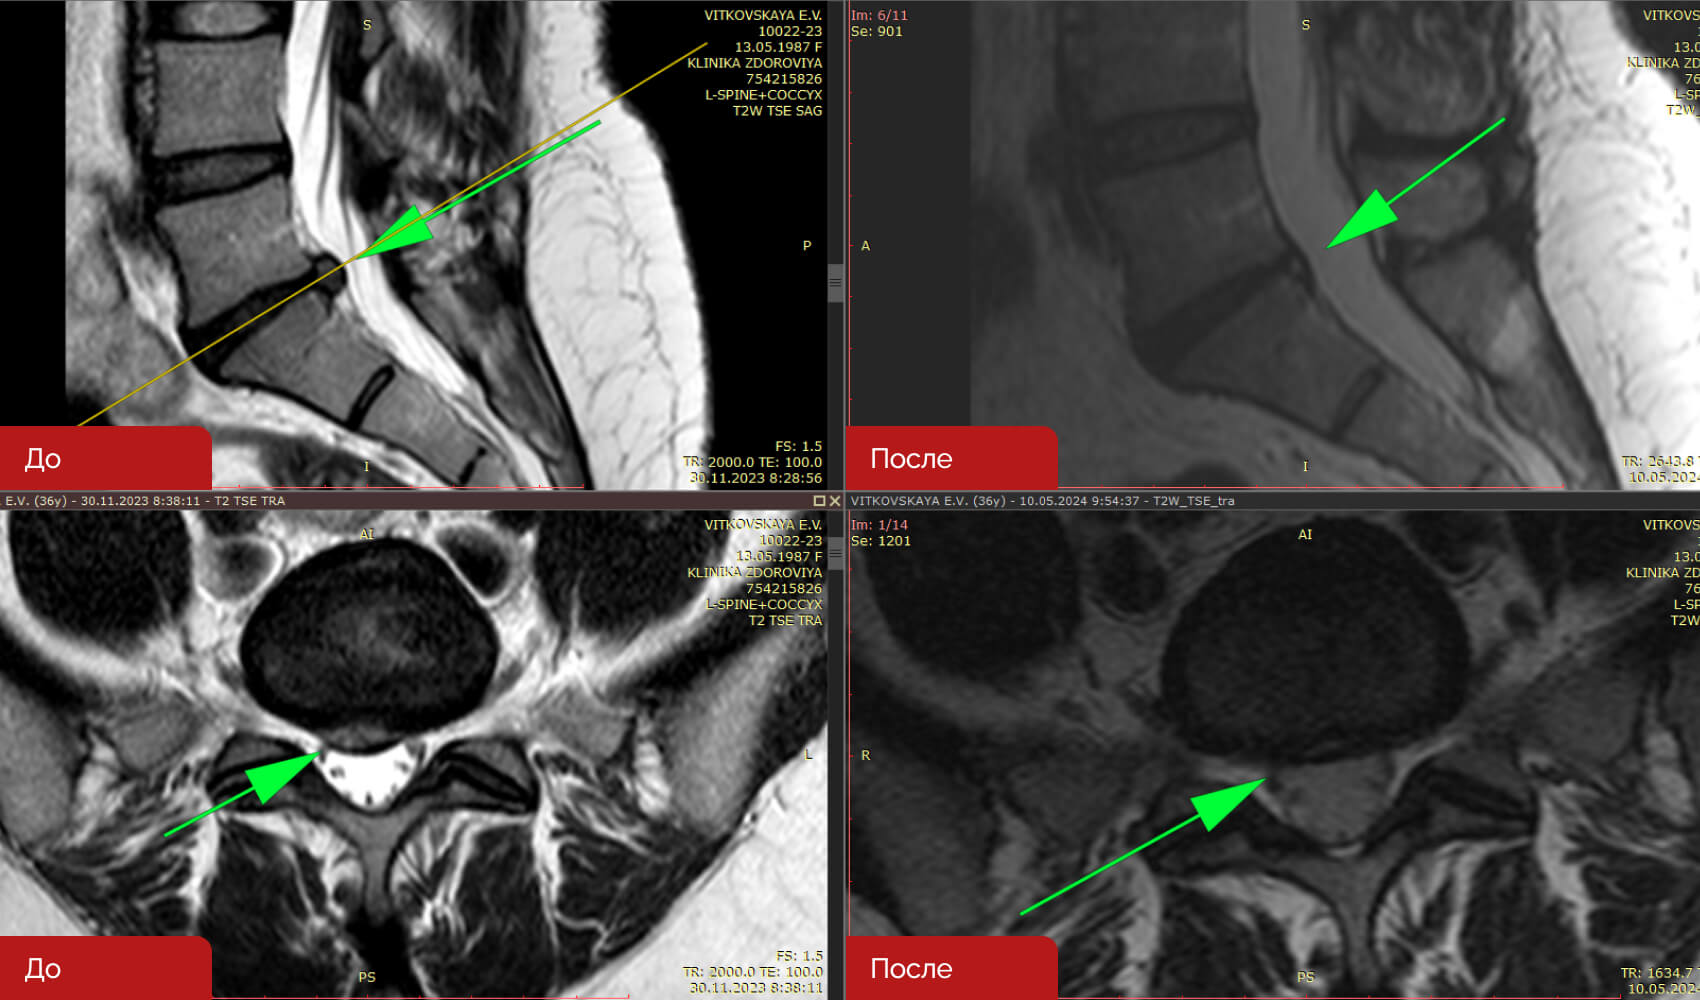

Резорбция грыж — это терапевтический процесс, направленный на уменьшение или полное исчезновение межпозвонковых грыж без хирургического вмешательства. Данный метод включает серию около 12 посещений клиники, три раза в неделю. После курса процедур, врач определяет время контрольного МРТ (обычно 2-3 месяца) для оценки результатов лечения.

Не все грыжи поддаются лечению данным методом. Решение о назначении резорбции принимается на основе анализа жалоб пациента, результатов МРТ и срока давности грыжи. Метод является безопасным и отличается отсутствием осложнений.

Кейс 1